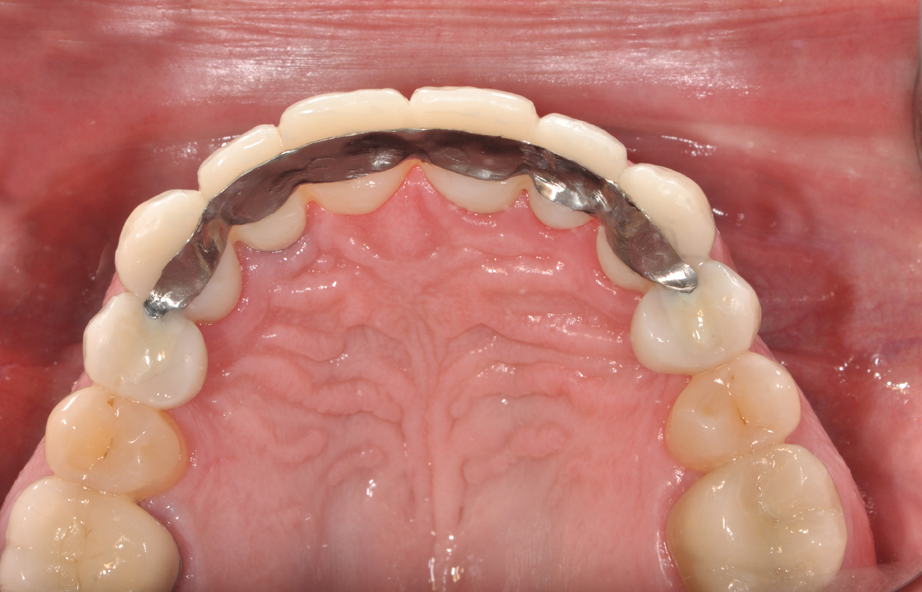

1. In Figure 1, we have an intraoral photograph of the patient with existing metal reinforced temporary bridge, which is planned for replacement with three implants and individual crowns. In Figure 2, we see another intraoral photograph after removing a PFM bridge, to reduce scatter in the DICOM image of the bone.

Fig. 1 Fig. 2